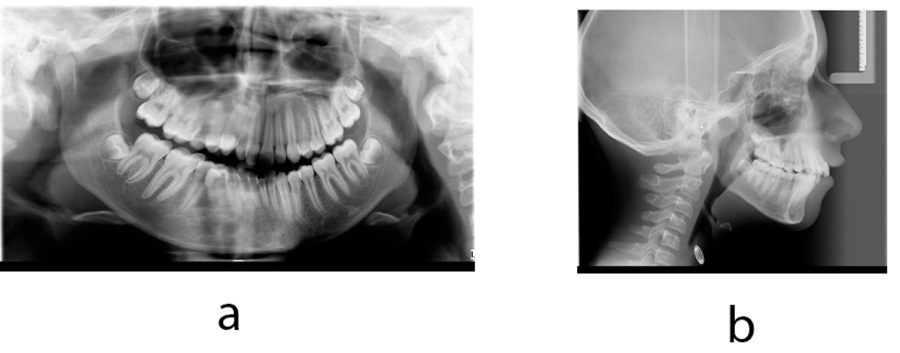

The patient had an asymmetric face with a convex facial profile. According to Schwarz typology [23], it was classified as an anteposition with retroinclinations (Fig. 1). Intraorally, the patient exhibited a Class II molar relationship, severely increased overjet (12 mm), and several carious deciduous teeth (Fig. 2). In addition to the general and dental history, photographs and impressions were taken, and panoramic and lateral x-rays were made (Fig. 3). Analysis of lateral cephalogram showed prognathic upper jaw and retrognathic lower jaw, skeletal Class II relationship, and borderline hyperdivergent (vertical) skeletal pattern (Fig. 3 and Table 1).

At the age of 12, new records were taken in order to plan the second phase of treatment. New photographs, intraoral scans, and x-rays were made (Fig. 5-7). After treatment, Class I molar relationship with normal overjet was obtained, the facial profile has improved. Panoramic x-ray indicated the presence of supernumerary root on the second right molar (Fig. 7). Analysis of lateral cephalogram showed improvement in parameters of sagittal relations, especially ANB, Wits appraisal, and SNA. There were no significant changes in vertical relations. Dental relations analysis noted proclination of both upper and lower incisors (Fig. 7 and Table 1).